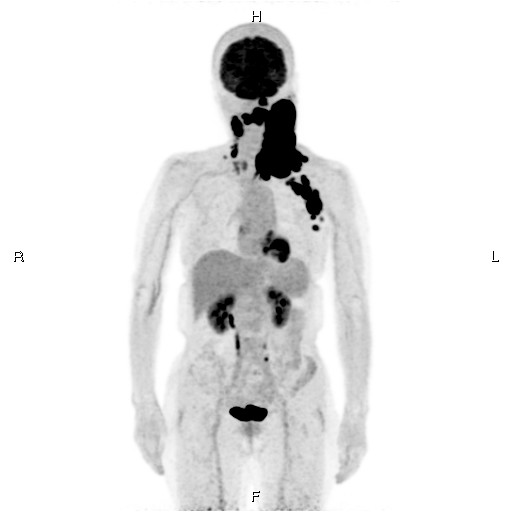

核医学検査

核医学検査は、微量の放射性医薬品を体内に投与し、その分布を画像化または数値化することで、病気の診断や血流・代謝などの情報を得る検査法です。使用する放射性医薬品はごく微量であり、被ばく量も少ない安全性の高い検査です。

当院では、キヤノンメディカル社製のPET/CT装置1台、GEヘルスケア社製のSPECT/CT装置1台を導入し、質の高い核医学検査を提供しています。